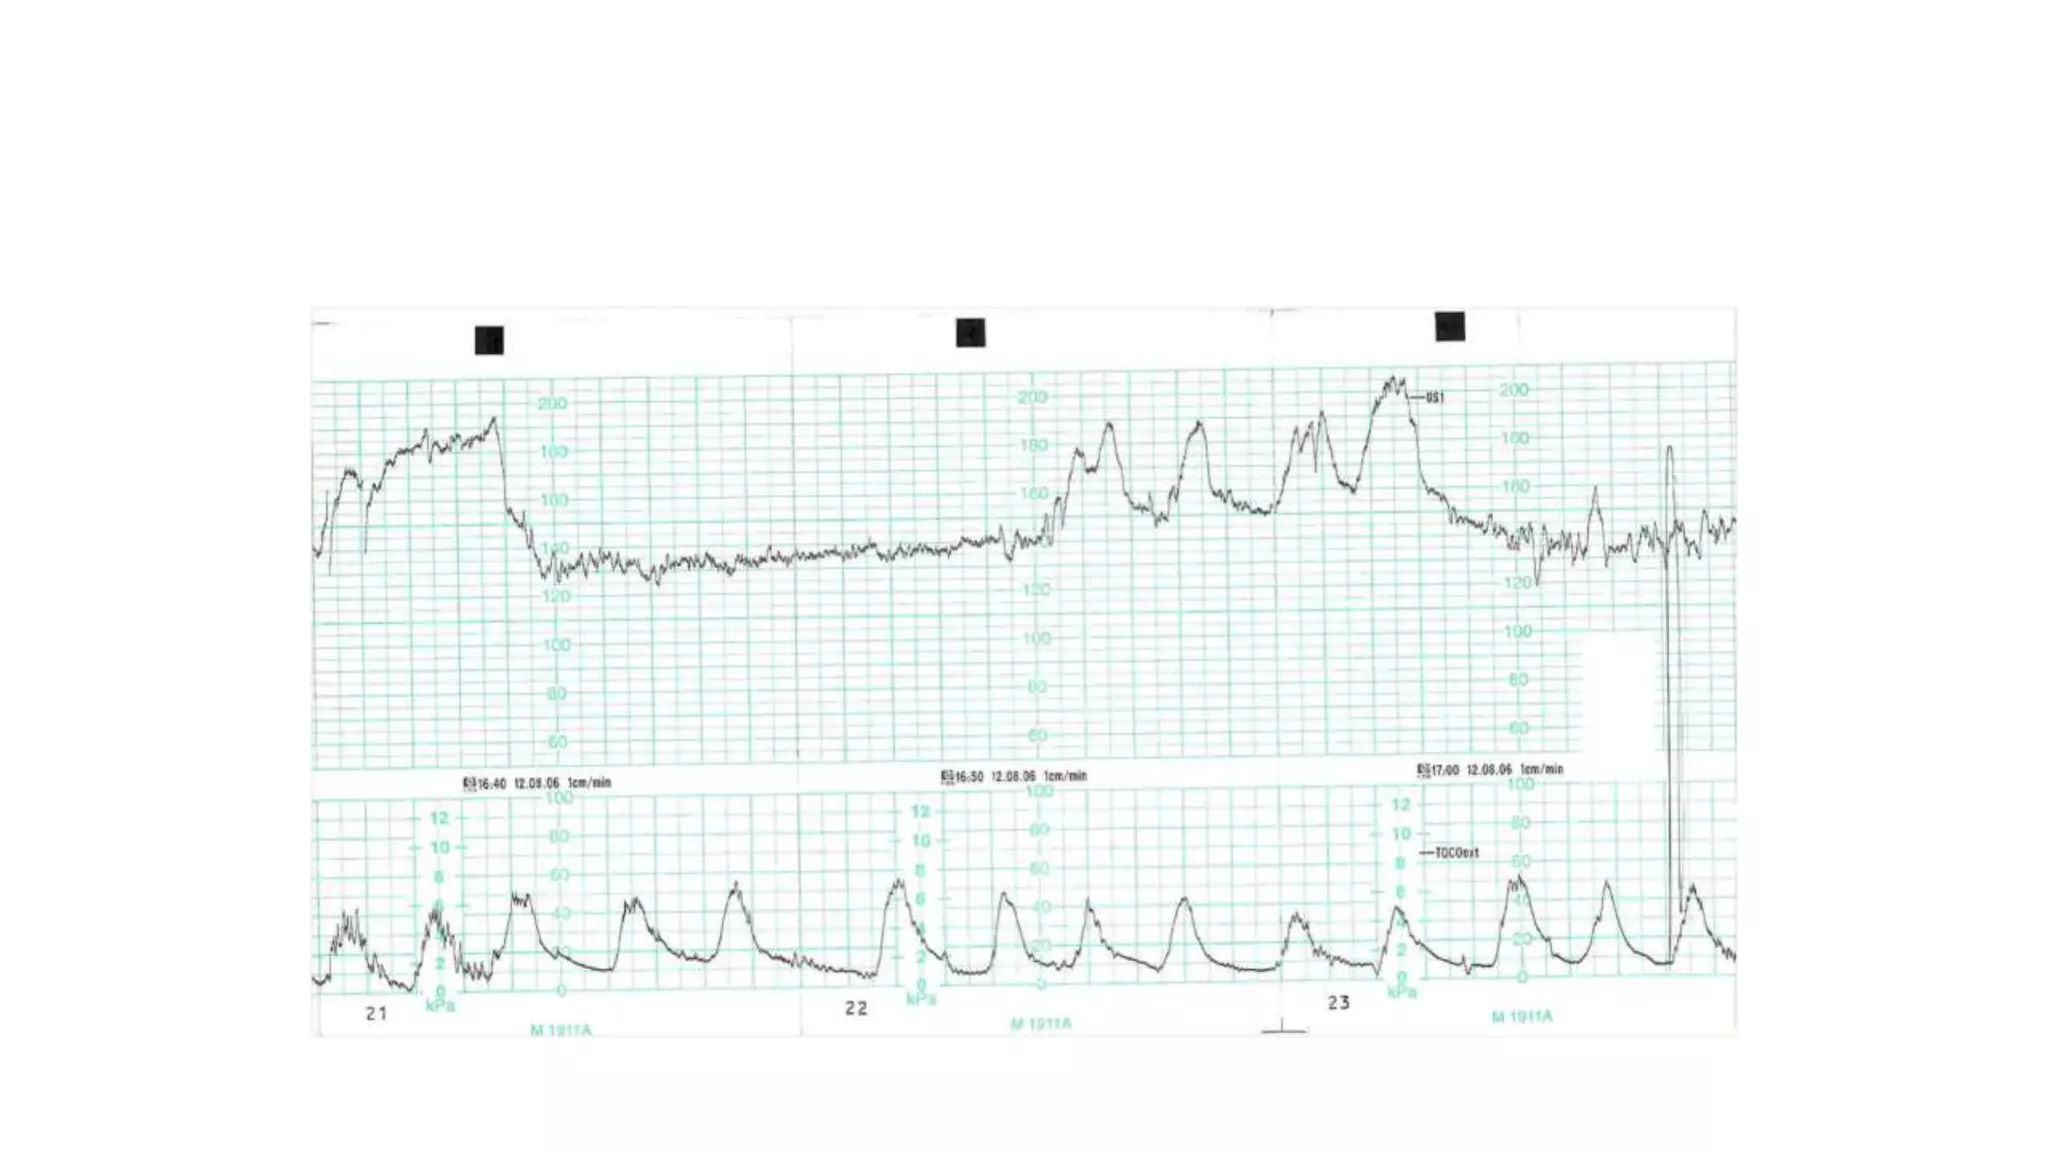

The document discusses key metrics for monitoring a baby's heart rate in utero, including the normal baseline rate of 100-160 bpm and variability. It also covers types of accelerations and decelerations that can occur, such as early or late, as well as bradycardia, which is an abnormally slow heart rate.